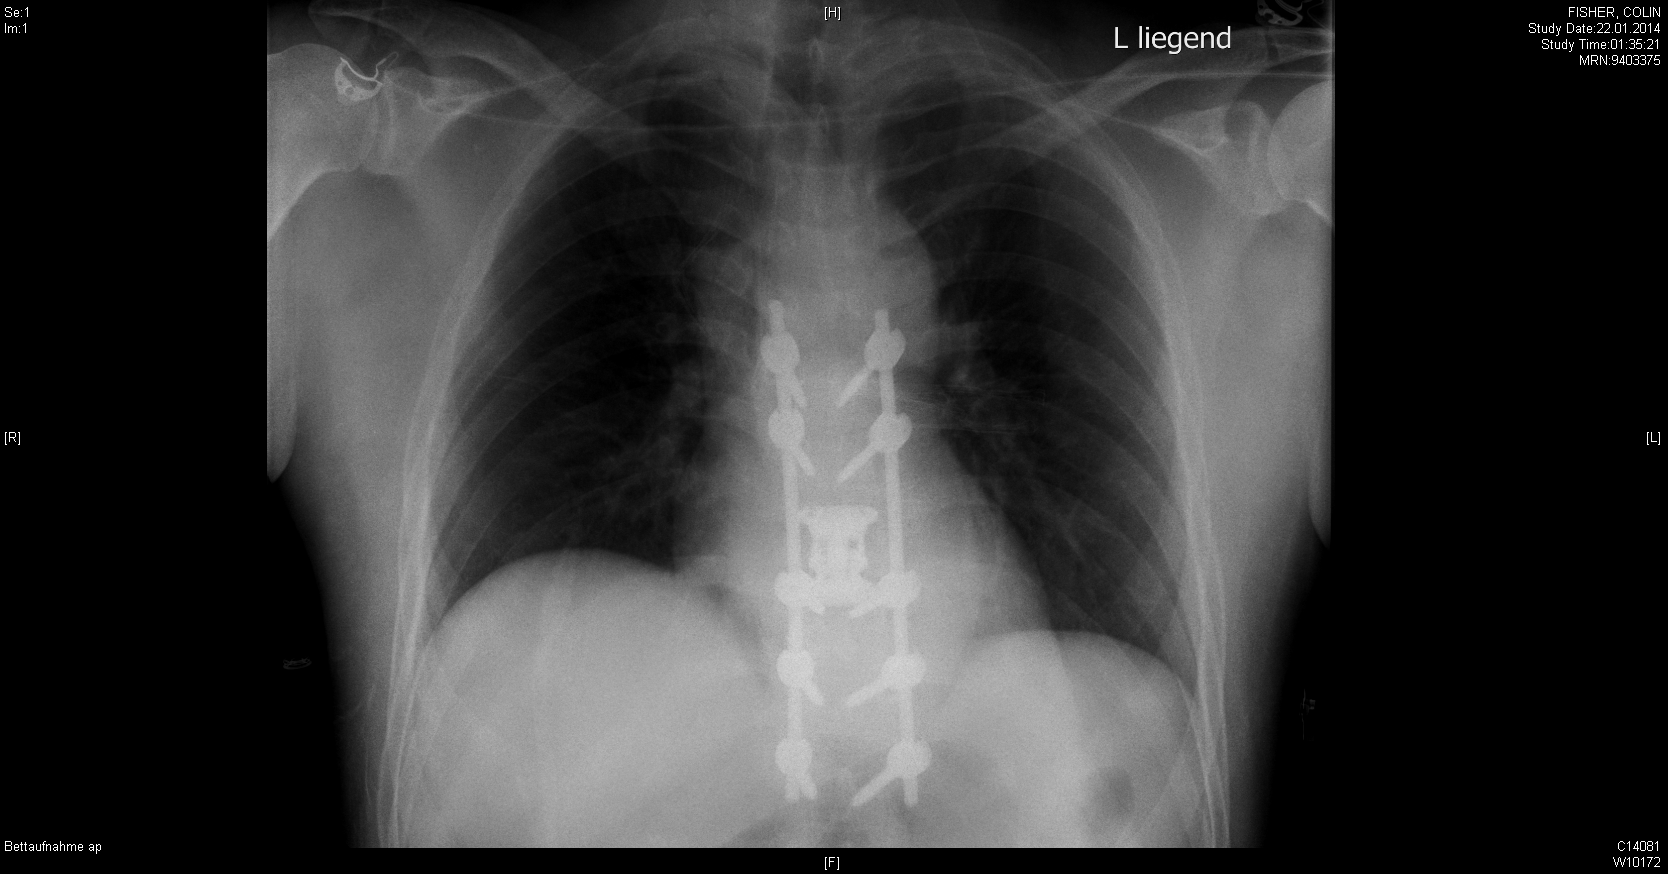

Photo: A momentous year. Colin breaking his back skiing in January prompted us to retire later that year. We’ve not looked back.